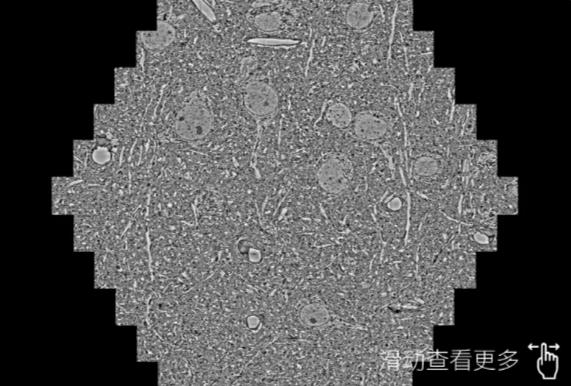

鼠脑切片。左图使用山西蔡司山西扫描电镜MultiSEM706对165μmx143pm面积区域成像,耗时仅需1.5秒。右图为鼠脑切片中30μm区域放大效果。样品由芝加哥大学B.Kasthuri提供。

使用蔡司高速山西扫描电镜MultiSEM对1mm²人脑皮层组织进行高分辨成像,并对其中的各种细胞结构进行三维重构分析。左图展示了2x3mm²组织平面中锥体神经元的三维重构效果。右图显示了局部体积神经元三维重构。图像由哈佛大学chtman实验室提供,渲染图由D. Berger 制作。